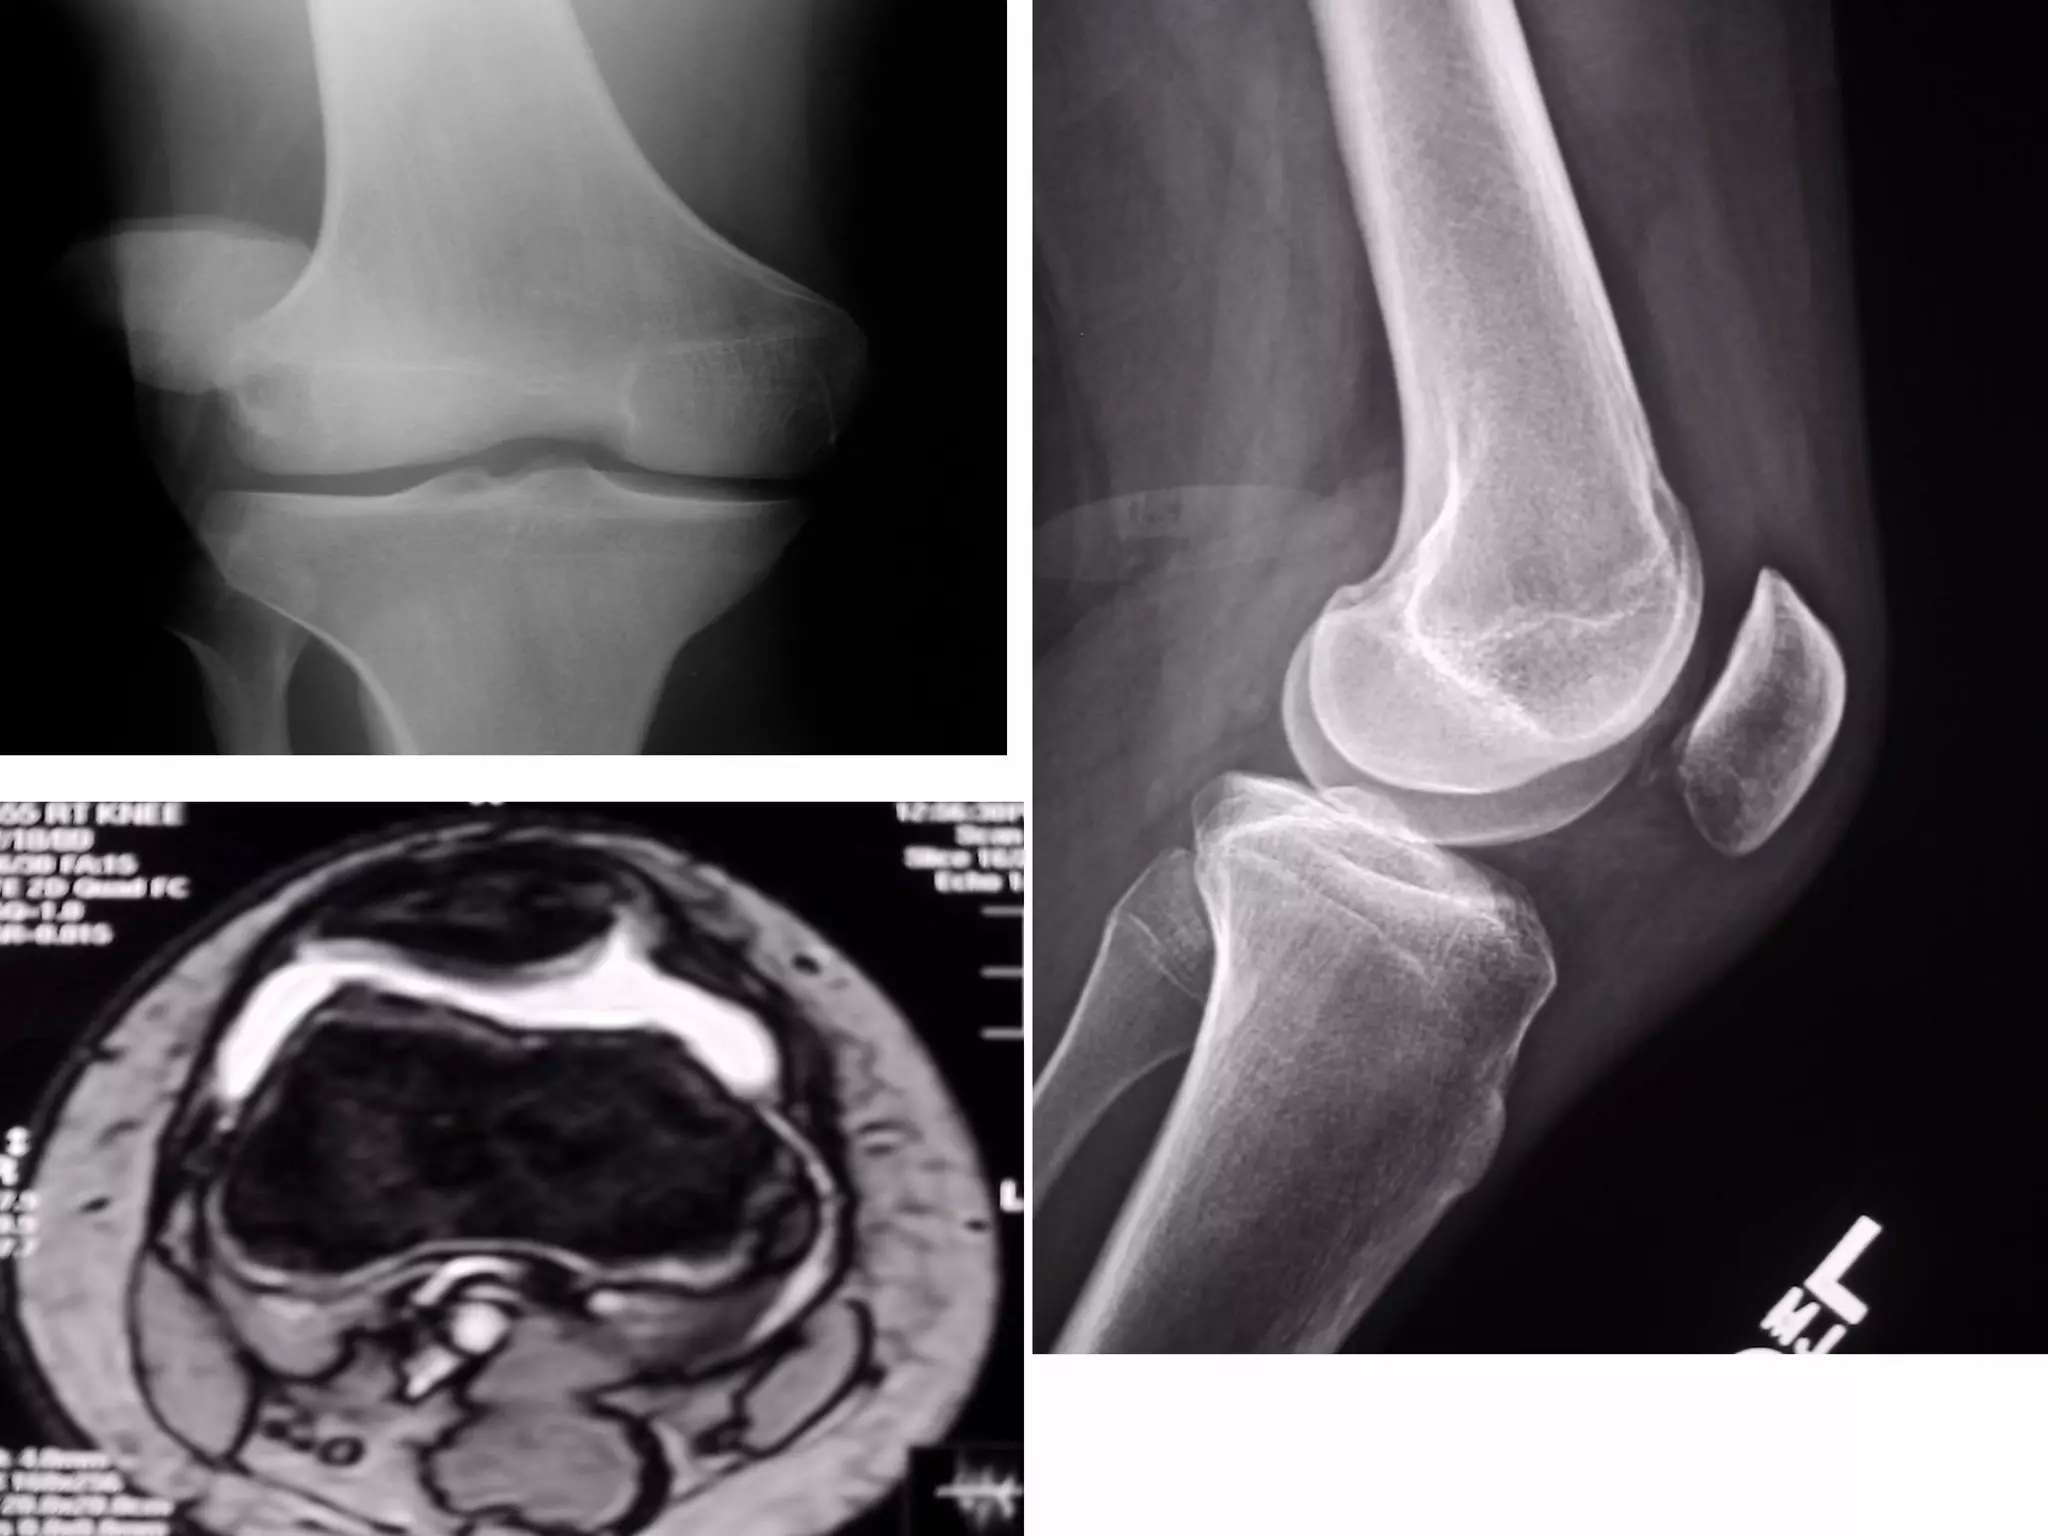

There are three types of patella dislocation: acute, recurrent, and habitual. Acute dislocation occurs suddenly due to quadriceps contraction with the knee flexed and results in the patella dislocating laterally, causing pain, swelling, and inability to straighten the knee. Recurrent dislocations are caused by ligament laxity or anatomical abnormalities and damage bones with repeated dislocations. Habitual dislocations occur every time the knee is flexed and present in early childhood.